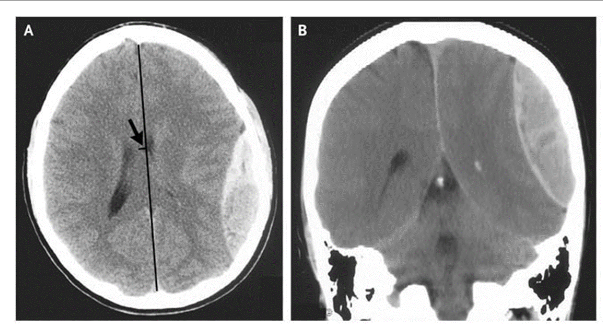

What is this pathology?

Epidural Hematoma

What is this pathology?

Subdural Hematoma